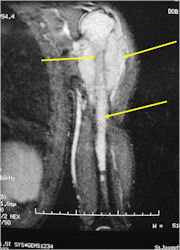

Radiographic Presentation

- Permeative or moth eaten bone destruction

- Soft Tissue Mass in 90% of of cases

- Ewing sarcoma is one of the most aggressive tumors

- Distant metastases (predominantly in lungs and other bones)

- Ewing sarcoma responds well to chemotherapy. Often there is a dramatic reduction in size of the tumor.